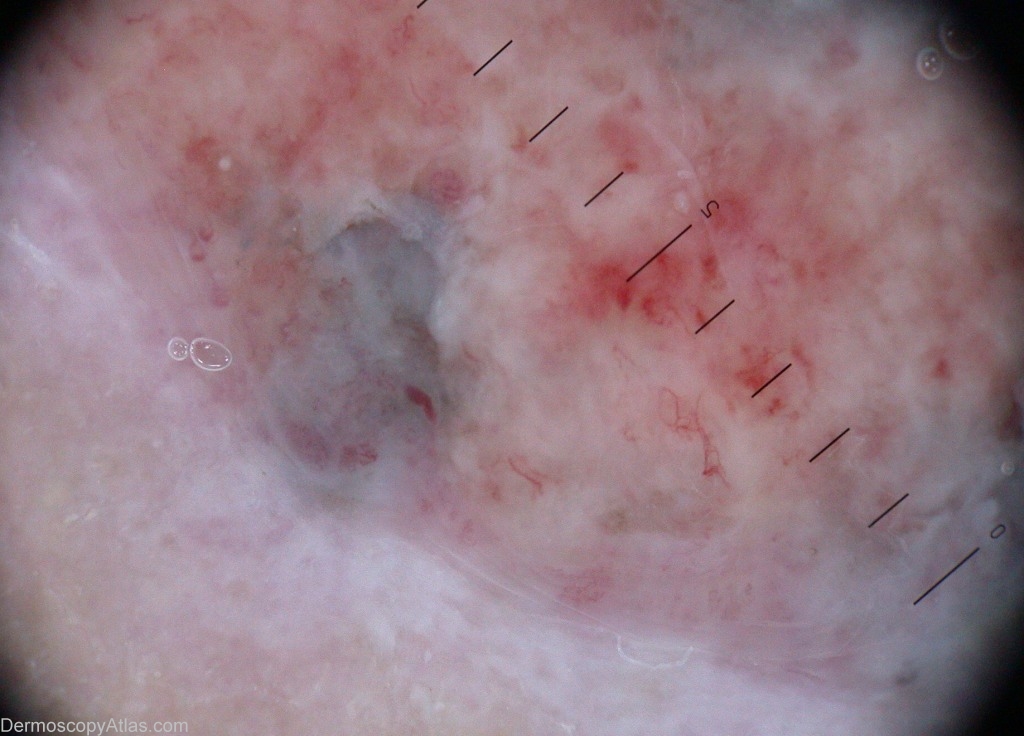

Diagnosis: Pigmented basal cell carcinoma

Description: Ulceration over the ankle, with a dark blue rim.

History: This lady came for a dark blue ulcerated lesion of a leg. Biopsy showed a pigmented basal-cell carcinoma. It is a twin case to case 189.